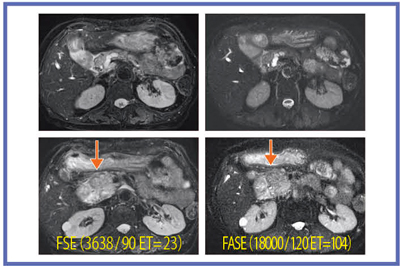

3Tではノイズの多さからFASEを使いたくなるが,図7のHCC症例のように,FASEのコントラストが十分でない場合もある。逆に,肝嚢胞と肝血管腫のように,FSEでは信号差が少なく,FASEでは嚢胞が著明な高信号を示す場合もあり(図8),現状ではFSEとFASEの両方の撮像が望ましいと考える。

図7 早期濃染するHCC症例

FASEでの腫瘍コントラストは,FSEよりも 不明瞭である。